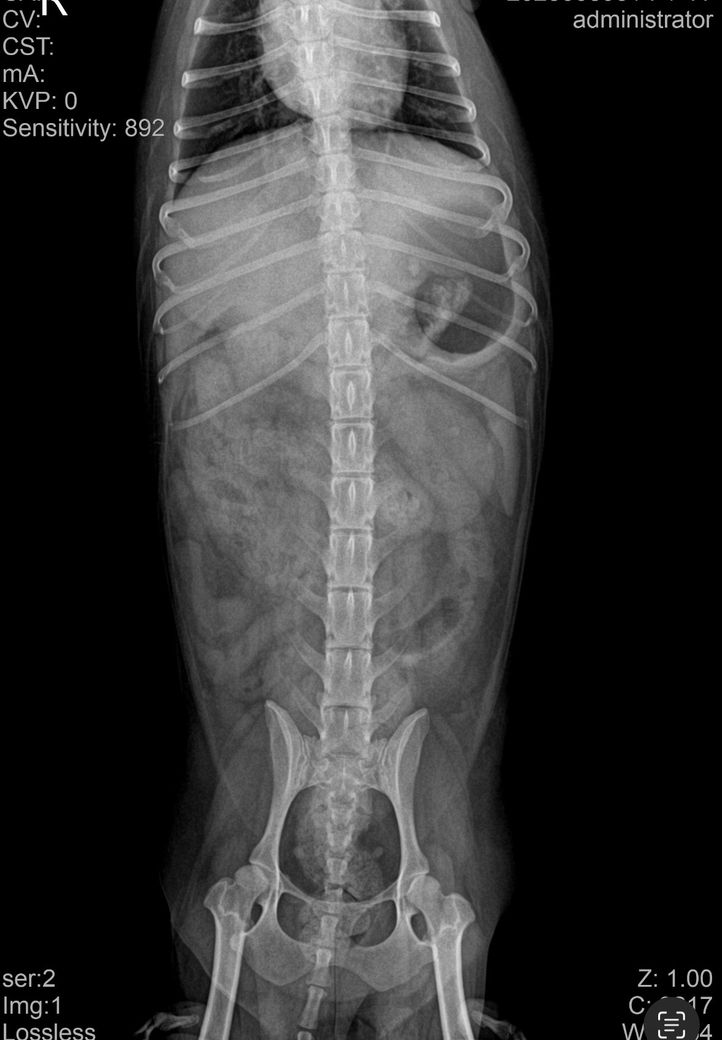

• 엑스레이, 초음파 검사 진행

• 검사 결과: 이물 가능성 있음, 확실하지 않음

4. 첨부 엑스레이에서 이물 여부 확인 가능 여부

엑스레이에서는 명확한 이물이 보이지 않을 수 있습니다. 플라스틱, 실, 천조각처럼 방사선 불투과성이 낮은 이물은 거의 보이지 않기 때문에 초음파로 확인하거나, 장 내 액체 정체나 장 운동 저하로 간접적으로 의심하는 경우가 많습니다. 물을 마셔도 바로 토하는 패턴은 위에서 내용물이 내려가지 못하거나, 위 자체가 심하게 자극된 상황에서 흔히 나타나며 이물 가능성과 위염 두 가지 모두에서 보일 수 있습니다.

첨부한 사진은 복배상의 사진밖에 없고 외측상이 없어 판독할 수 없습니다. 방사선 사진은 원래 앞사진, 옆사진 이렇게 최소 2장이 필요합니다.